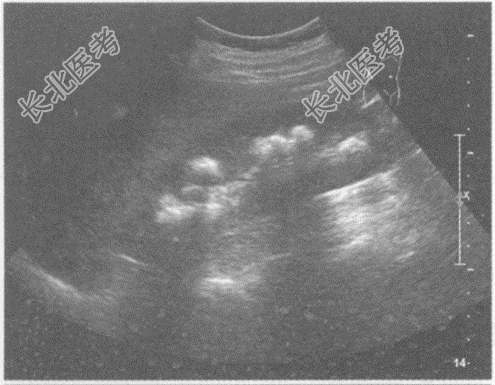

- 单项选择题临床资料:女, 25岁,因反复四肢麻痹10年, 腰部疼痛、肉眼血尿3月余入院。

化验检查:尿常规红细胞3+。

超声综合描述: 双肾形态、大小正常,沿肾锥体分布可见多个强回声光团, 后伴声影。

超声提示: A、双肾钙乳症

B、双肾海绵肾

C、双肾多发结石

D、双肾多发钙化

E、双肾错构瘤